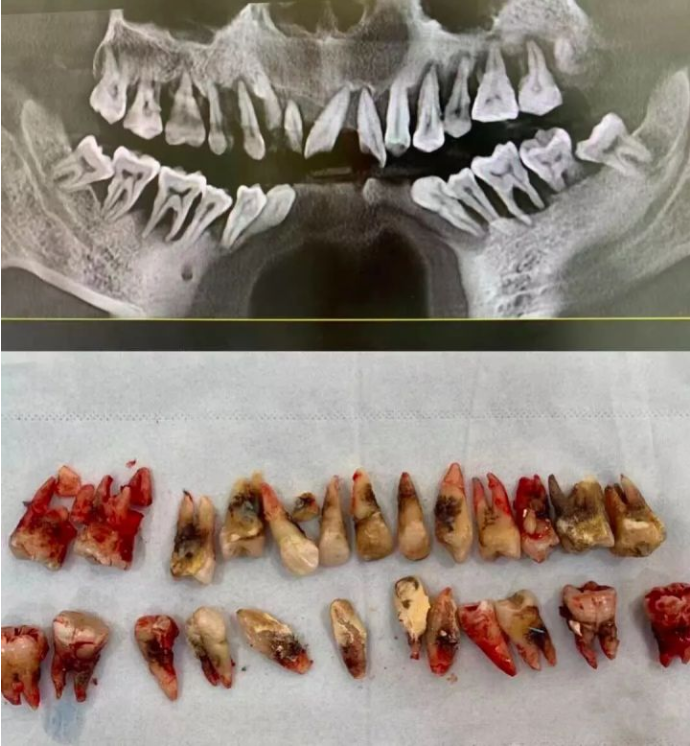

湖北省孝感市中心医院口腔科副主任医师徐勇刚曾在其公号发文介绍,一个30多岁的小伙子,只是因为“牙齿松动”来就诊。

但等待他的,却是晚期牙周炎患者的最终归宿——全口牙松动、拔除。

牙周炎患者被拔除的牙齿(@西安牙医老聂 图)↓↓↓

换句话说,他看起来一颗牙也不缺,但其实一颗牙也没有了——